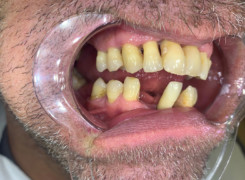

Pan Ryszard trafił do Naszego Gabinetu z jasno sprecyzowanym oczekiwaniem. Miał 84 lata i chciał odzyskać możliwość swobodnego spożywania posiłków oraz poprawienia sobie komfortu życia a także prosił aby przywrócić mu piękny uśmiech jakim cieszył się przed laty. Już na początku pierwszej rozmowy zastrzegł, że interesuje go wyłączenie rozwiązanie uzupełnieniem protetycznym stałym. Nie miał zamiaru użytkować żadnych protez ruchomych. Mając na uwadze powyższe wykonaliśmy Panu Ryszardowi zdjęcie pantomograficzne oraz badanie tomograficzne szczęki i żuchwy na postawie których zapanowywaliśmy Pacjentowi optymalne rozwiązanie – stałe uzupełnienie protetyczne w postaci 28 koron cyrkonowych zamontowanych do dwóch belek cyrkonowych które będą przymocowane do 16 implantów w konfiguracji 8 wszczepów w szczęcie 8 w żuchwie. Po omówieniu powyższego planu przystąpiliśmy do Wspólnej pracy której efekty w poszczególnych etapach prezentujemy poniżej.